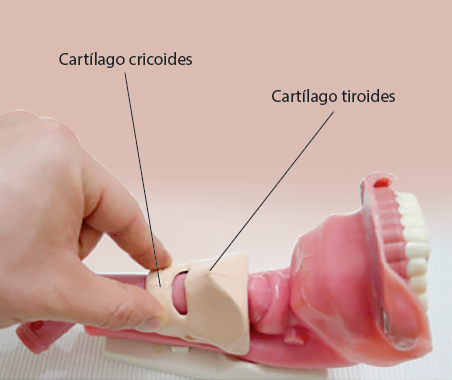

En la nota pre y postquirúrgica del 10 de agosto de 2018, se describió que a la paciente se le realizó aspiración de la sonda nasogástrica previo a la cirugía y durante el procedimiento anestésico, además de inducción de secuencia rápida para evitar la broncoaspiración. Ello consta de un proceso ordenado de pasos que termina con el aseguramiento de la vía aérea, disminuyendo la probabilidad de presentar complicaciones como consecuencia de la hipoxemia (disminución anormal de la presión parcial de oxígeno en la sangre arterial), dentro de muchas otras, tales como broncoaspiración, intubación esofágica, lesión de la vía aérea, etc.10, además de la maniobra de Sellick que es la realización de presión sobre el cartílago cricoides para ocluir el esófago superior contra las vértebras cervicales (5ª) y así prevenir la regurgitación de contenido gástrico a la faringe11 (figura 2).

Describa la maniobra de Sellick:

Realización de presión sobre el cartílago cricoides para ocluir el esófago superior contra la vértebra cervical (6ª) y así prevenir la ingurgitación de contenido gástrico a la faringe.

Realización de presión sobre el cartílago cricoides para ocluir el esófago superior contra la vértebra cervical (5ª) y así prevenir la regurgitación de contenido gástrico al esófago.

Realización de presión sobre el cartílago tiroides para ocluir el esófago inferior contra la vértebra cervical (5ª) y así prevenir la regurgitación de contenido gástrico a la faringe.

Realización de presión sobre el cartílago cricoides para ocluir el esófago superior contra la vértebra cervical (5ª) y así prevenir la regurgitación de contenido gástrico a la faringe.